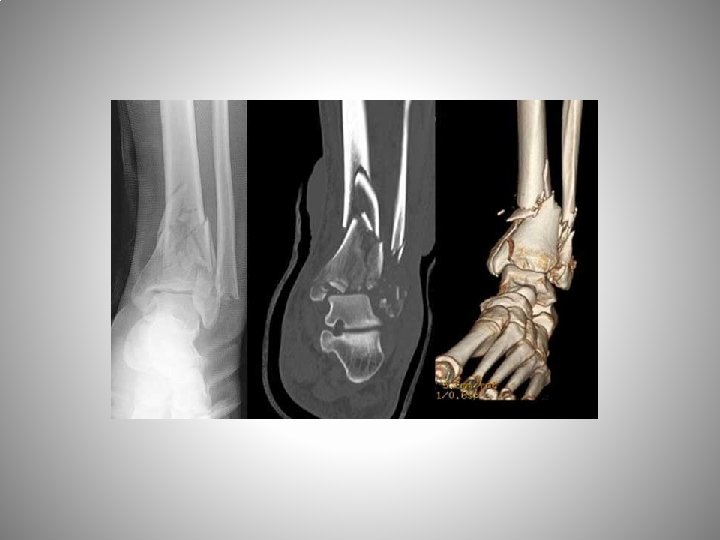

% 70 den fazla post travmatik Ayak bilek travmaları yeterli ve anatomik tedavi edilmeli !!!! a. Rotasyonel ayak bilek kırıkları b. Pilon kırıkları c. Malleol kırıkları d. Ligamentöz instabiliteler e. Talusun kondral lezyonları

73, ERKEK, 10 YILLIK YAKINMALAR-ARALIKLI, GENİŞ OSTEOKONDRAL LEZYON